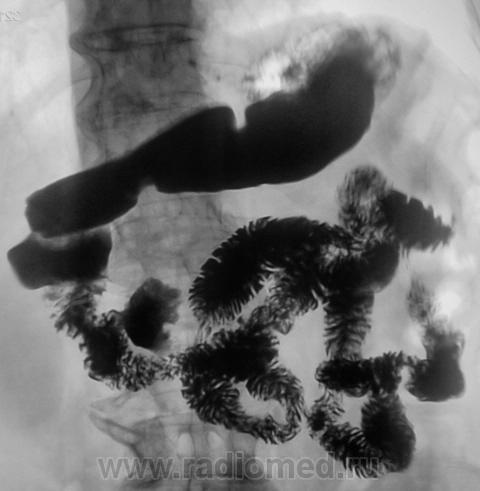

Пациент направлен на рентгенологическое исследование ЖКТр. Основная патология - толстая кишка.

Но вот - "дивертикул", ну, что-то не нравится мне этот дивертикул. Что посоветуете уважаемые коллеги?

Мне в ентом дивертикуле тоже не все понравилось. Интрадивертикулярная гиперплазия. Эндоскописты в то время не добрались. Правда, и пациент пропал, контроля не было.

Такая картинка очень даже встречается...это из свежих.....имеется ввиду "двойной" дивертикул...

Мы видим единственный снимок. Дивертикул не был ригидным? Форма его менялась?

Да, форма менялась, ригидности не наблюдалось...вопрос о малигнизации в данном случае не ставился...просто пример т.н. "двойного" дивертикула...

Извините,Петрович...влез со свом дивертикулом не совсем к месту...но уж больно заковырист по форме....и еще - в дивертикулах, особенно средних и крупных при тонких или относительно тонких шейках, весьма часты встречаются безоары...есть и наблюдение...есть и свидетельства и записи эндоскопистов. Посему очень даже можно "пролететь" по его содержимому и стенкам...